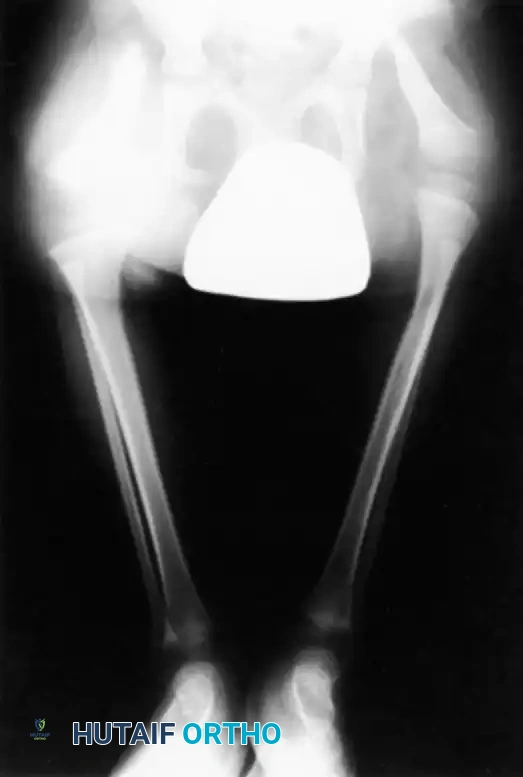

This condition represents a broad spectrum of deformities, ranging from the total absence of the tibia (the most severe form) to mild hypoplasia of the tibia (the least severe form). The incidence is exceedingly rare, estimated at one in 1 million live births, and the condition presents bilaterally in approximately 30% of affected patients.

Clinically, the involved leg is significantly shortened. The fibular head is often palpable, particularly if it is proximally displaced into the popliteal fossa. The foot is typically held in severe, rigid equinovarus, and the hindfoot is profoundly stiff.

- Type 1A Deformity: There is complete radiographic absence of the tibia and a hypoplastic distal femoral epiphysis compared with the contralateral normal side.

- Type 1B Deformity: There is no radiographic evidence of an ossified tibia; however, the distal femoral epiphysis appears more normal in size and shape. This distinction is critical because Type 1B deformities possess a proximal tibial cartilaginous anlage that can be expected to ossify over time. Modern imaging techniques, such as high-resolution ultrasound and MRI, are mandatory to identify this cartilaginous anlage.

- Type 2 Deformity: A proximal tibia of varying size is present and ossified at birth. The fibula is usually normal in size, but the fibular head is proximally dislocated.